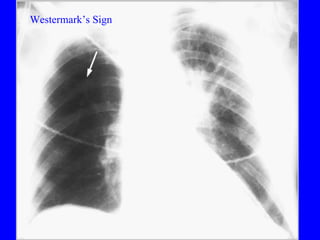

Pulmonary embolism (PE) is a common and potentially fatal condition where blood clots block arteries in the lungs. An estimated 5 million venous thromboses occur annually worldwide, with 10-30% of cases resulting in PE. Risk factors include immobilization, surgery, cancer, and estrogen use. Diagnosis involves assessing clinical probability based on symptoms and risk factors, followed by tests like D-dimer, chest imaging, ultrasound, V/Q scan, CT, or angiogram. Treatment aims to prevent further clotting with anticoagulants like heparin and warfarin, provide supportive care, and in some severe cases utilize thrombolysis or embolectomy.